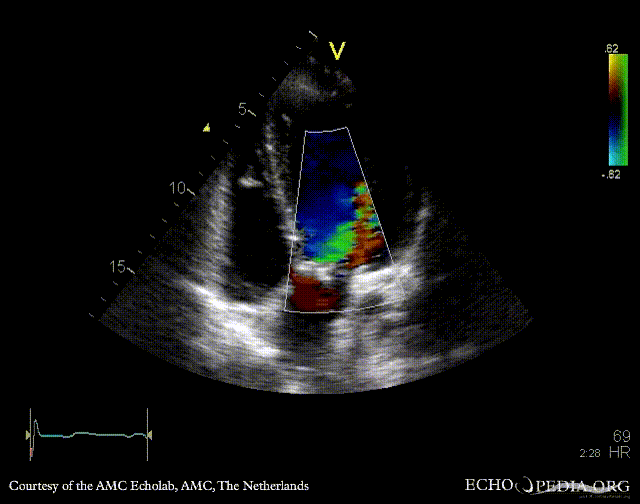

E00341.gif E00342.gif

A5CH: Color Doppler, moderate aortic regurgitation PSAX: bicuspid aortic valve